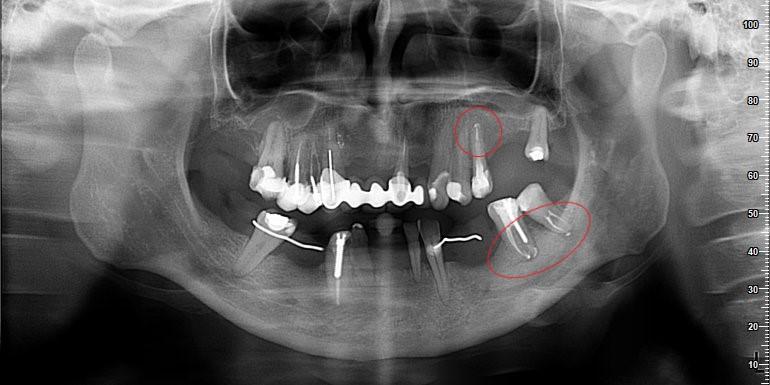

Leczenie kanałowe jest leczeniem skutecznym. Prawidłowe leczenie kanałowe sprawia, że ząb przestaje być ogniskiem zakażenia, a tkanki wokół goją się. Wyleczenie zęba powoduje, że przyczyna choroby tkanek około zębowych [na RTG widzimy jedynie chorobę kości] zostaje usunięta. Eliminacja przyczyny choroby umożliwia gojenie się zmian chorobowych.

Na poniższych zdjęciach RTG – WIDAĆ GOJENIE ZMIAN ZAPALNYCH KOŚCI.

Nie jest prawdą, że leczenie kanałowe w każdym przypadku jest szkodliwe. Ogniskami zakażenia są zęby martwe, nieprzeleczone kanałowo, zęby z nieprawidłowym leczeniem kanałowym i to właśnie one są zagrożeniem i powinny być eliminowane.

W naszej poradni leczenie prowadzą lekarze endodonci, doświadczeni w leczeniu kanałowym, jakość leczenia podnosi stosowanie mikroskopu oraz kontrola radiologiczna. Nasz tomograf umożliwia uwidocznienie kanałów oraz sprawdzenie jakości ich wypełnienia.